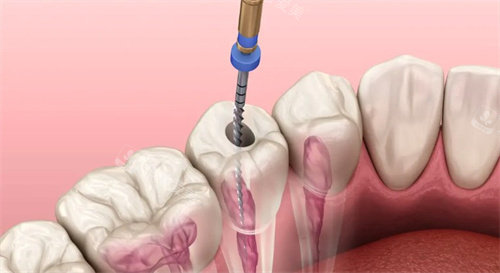

根管治疗动画示意图

根管治疗流程图展示